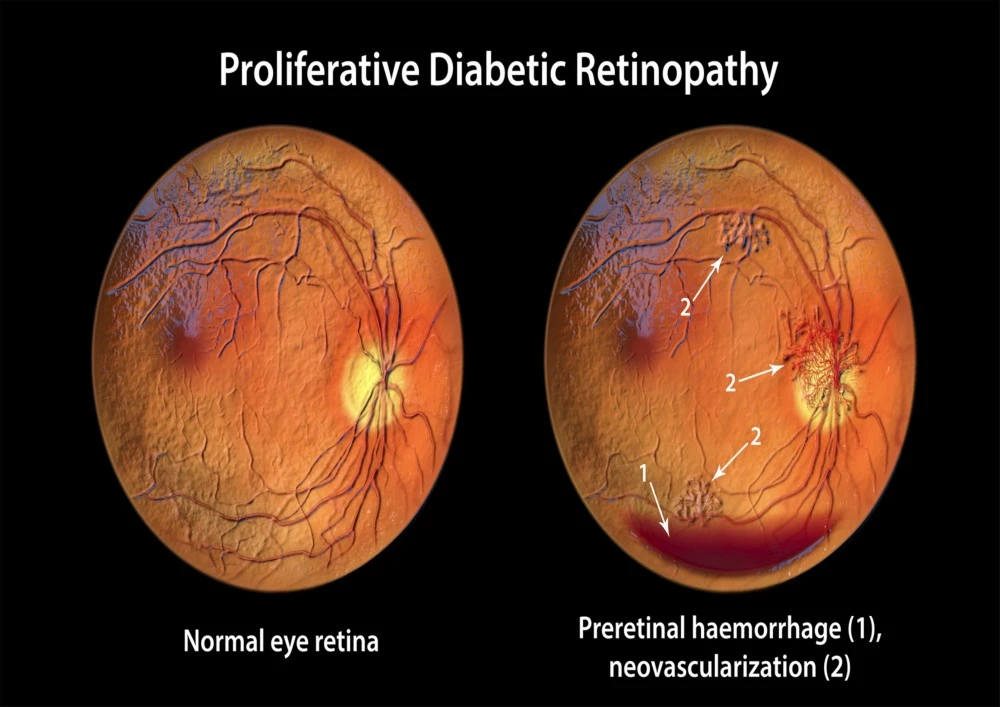

3. Proliferative Diabetic Retinopathy

This advanced stage is characterized by the growth of abnormal new blood vessels (neovascularization). These vessels are fragile and prone to bleeding, which can lead to vitreous hemorrhages, retinal detachment, and severe vision impairment. Immediate consultation with a retina specialist is crucial at this stage.

Can diabetic retinopathy lead to retinal detachment?

Yes, diabetic retinopathy can increase the risk of retinal detachment, particularly in proliferative stages. Abnormal blood vessels may grow on the retina and form scar tissue. Over time, this tissue can contract, pulling the retina away from its normal position, causing traction retinal detachment. Symptoms may include sudden flashes of light, floaters, or a curtain-like shadow across vision. Retinal detachment is a serious complication that requires urgent surgical intervention, such as vitrectomy, to prevent permanent vision loss. Regular eye exams can detect early signs and allow timely treatment to reduce the risk of detachment.

Can diabetic retinopathy cause glaucoma?

Diabetic retinopathy can indirectly contribute to glaucoma, particularly neovascular glaucoma. In advanced stages, abnormal blood vessels may grow in the iris and drainage channels of the eye, increasing intraocular pressure. Elevated pressure can damage the optic nerve, leading to glaucoma. This form of secondary glaucoma is serious and requires prompt intervention, often combining medications, laser therapy, or surgery to control eye pressure. Managing diabetic retinopathy early and monitoring eye health can reduce the risk of developing glaucoma and other vision-threatening complications.